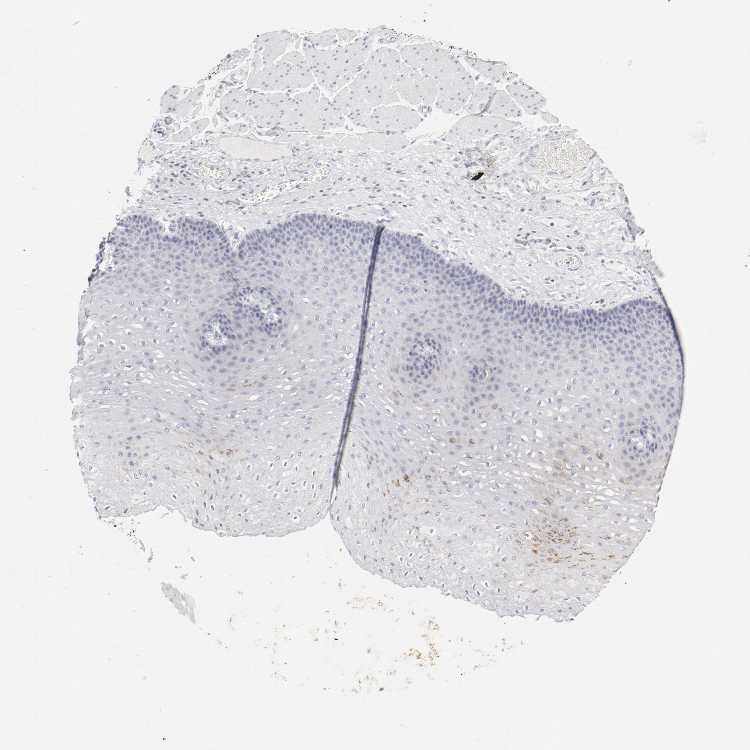

ESOPHAGUS - Antibody stainingi

Antibody staining in the annotated cell types in the current human tissue is reported as not detected, low, medium, or high, based on conventional immunohistochemistry profiling in selected tissues. This score is based on the combination of the staining intensity and fraction of stained cells.

Each image is clickable and will lead to virtual microscopy that enables deeper exploration of all samples and also displays staining intensity scores, fraction scores and subcellular localization as well as patient and tissue information for each sample.

Antibody HPA004723Antibody CAB004458Antibody CAB072871

Squamous epithelial cells Not detectedNot detectedNot detected